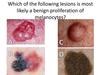

Question 2

C is correct

A is Basal cell Carcinoma

B is a Melanoma

C is a benign Nemus

D Seborrheic Keratosis

Question 3

Which of the following lesions is of most concer?

Correct Answer: A

A Melanoma

B Seborrheic Keratosis

C & D Benign Melanocytic Lesions